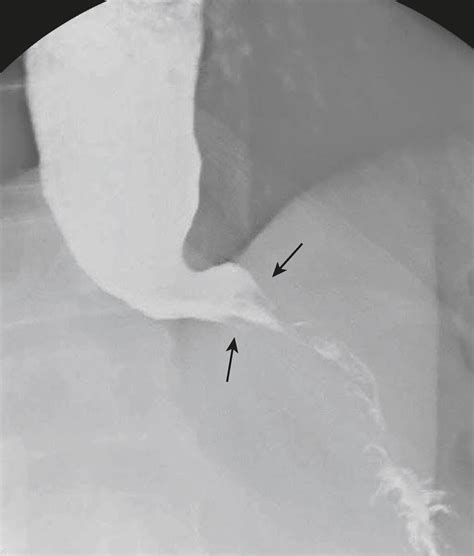

The Birdbeak Sign is a distinctive radiographic appearance seen on abdominal X-rays or CT scans. It is characterized by a tapered, beak-like appearance of the sigmoid colon, which indicates a twist or volvulus. This sign is crucial because it helps radiologists and gastroenterologists identify the presence of a sigmoid volvulus, which is a medical emergency requiring immediate intervention.

Interpreting the Birdbeak Sign During Flexible Sigmoidoscopy

During a flexible sigmoidoscopy, the presence of a Birdbeak Sign can be confirmed by visualizing the twisted sigmoid colon. The sigmoidoscope allows for a direct view of the colon, enabling the gastroenterologist to assess the extent of the twist and the condition of the colonic mucosa. This direct visualization is crucial for confirming the diagnosis and planning the appropriate management strategy.

The Birdbeak Sign Flexible Sigmoidoscopy is a critical tool in the diagnosis and management of sigmoid volvulus. By understanding the radiographic appearance of the Birdbeak Sign and utilizing flexible sigmoidoscopy, healthcare professionals can accurately diagnose and treat this condition. Prompt intervention is essential to prevent complications and ensure the best possible outcomes for patients. Regular follow-up and preventive measures can help reduce the risk of recurrence and improve long-term health.